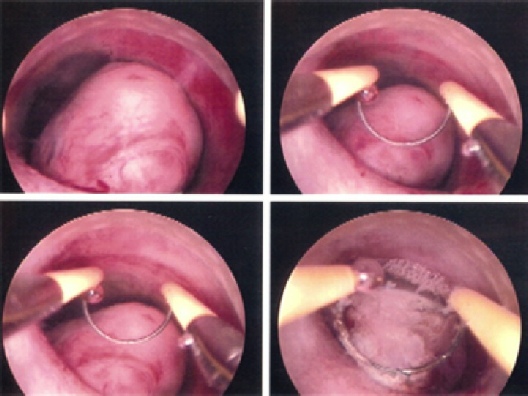

Abnormal Periods